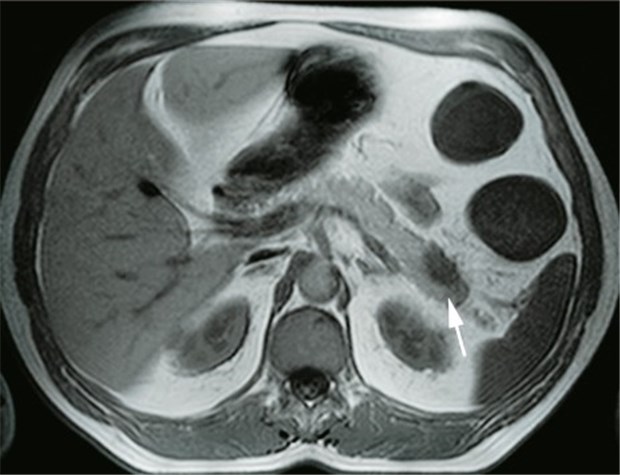

MRE: Raumforderung (Pfeil) im Pankreasschwanz eines Morbus-Crohn-Kranken. Spätere Diagnose: Pankreas-Ca.

© Foto: Herfarth et al., Innere Medizin, Uni Regensburg

Mit der MRE können pathologische Befunde nicht nur im, sondern auch außerhalb des Darms aufgedeckt werden. Das belegt etwa eine Studie mit über 1000 Patienten, die wegen chronisch entzündlicher Darmkrankheit, wegen Verdachts auf eine solche Erkrankung oder wegen unklarer abdomineller Symptome und Befunde mit MRE untersucht worden waren. In der Untersuchung wurde bei 600 Patienten insgesamt 1113 mal ein pathologischer Befund außerhalb des Darmes, etwa der von Abszessen oder eines Tumors, erhoben. "Diese Ergebnisse verdeutlichen den entscheidenden Beitrag von Schnittbildverfahren in der Untersuchung des Bauchraums", so Autor Schölmerich.